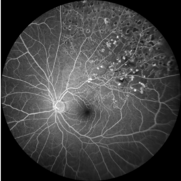

Severe NVD Leakage During a Fluorescein Angiogram

Mar 26 2018 by Kristen Wagner

Fluorescein angiogram image of the disc of a left eye showing leakage (NVD). Patient is a young woman with uncontrolled Diabetes Type II with severe neovascularization of the disc (NVD) and PDR.

Photographer: Kristen Wagner, COT, OSC

Condition/keywords: diabetes, fluorescein leakage, neovascularization (NV), neovascularization of the disc (NVD), optic disc, optic nerve, proliferative diabetic retinopathy (PDR)